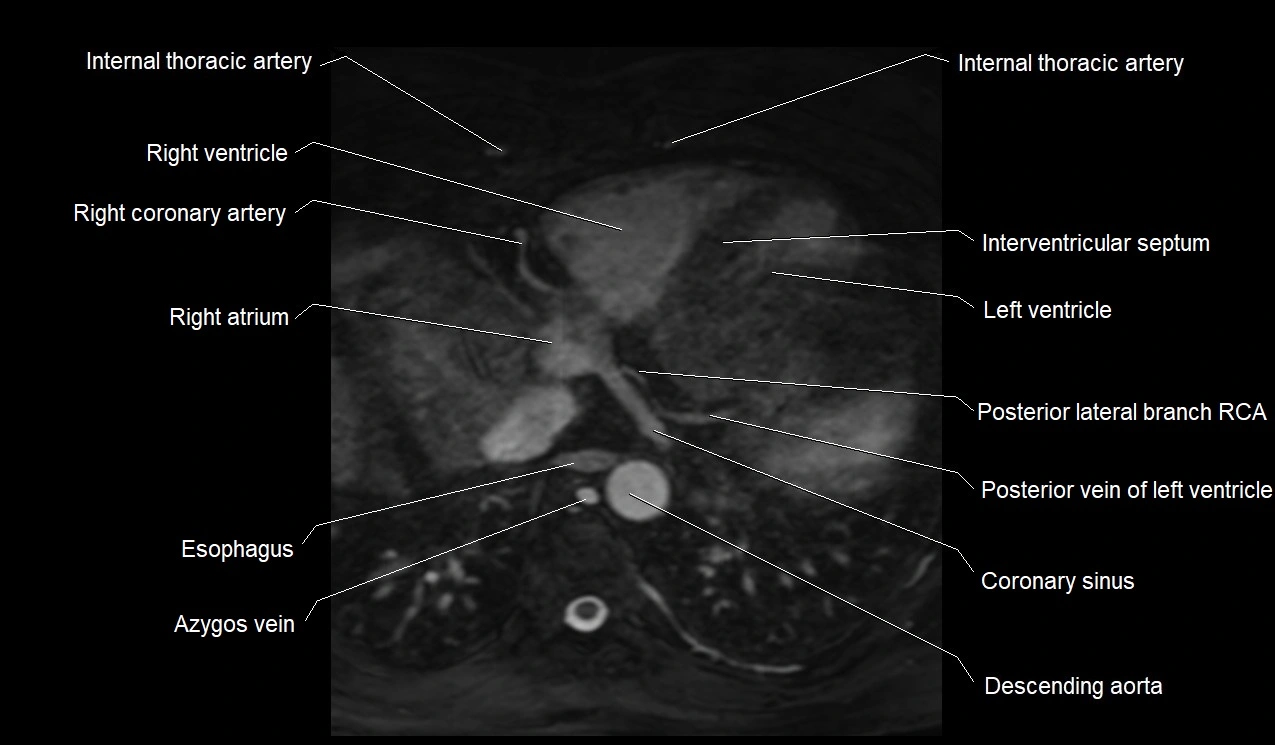

MRI image